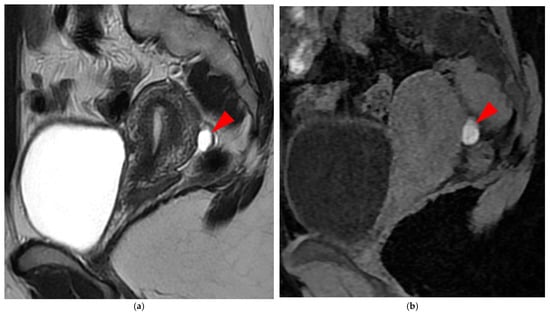

A type 5A USL (Figure 6) is nodular with a smooth contour.

Figure 6. Pelvic MRI scans of two patients with HTD type 5A USLs. (a,b) Sagittal T2WI: nodularity with regular margins (arrows) within the right USL (arrowheads).